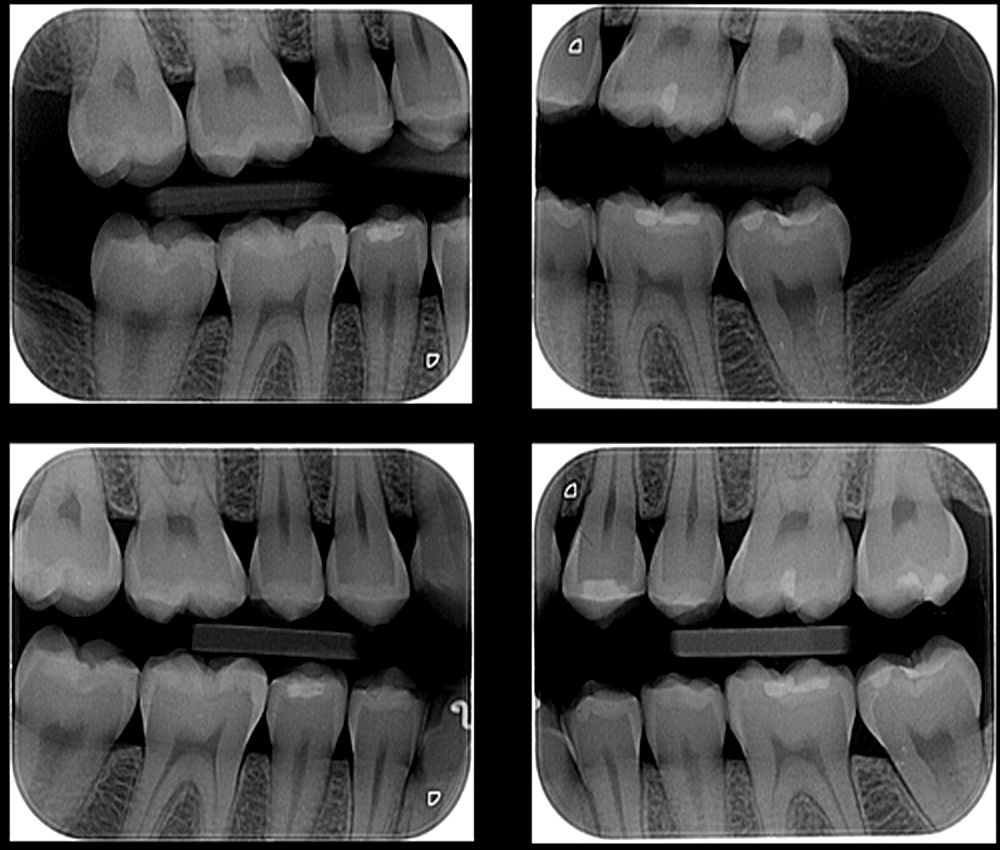

A radiografia interproximal. A técnica interproximal ou bite wing inclui, em um mesmo filme, as coroas dos dentes superiores, as coroas dos dentes inferiores e a crista óssea alveolar de uma determinada região, geralmente pré-molares ou molares. A radiografia interproximal é o exame de escolha para a detecção da presença de lesões.

A radiografia interproximal ou RX bite wing é um exame usado em medicina dentária e que serve essencialmente para observar as coroas dos dentes superiores e inferiores numa só imagem. Normalmente, essa imagem consegue abranger a coroa completa de 2 a 3 dentes de cada maxilar. O termo "bite wing" significa, numa tradução à letra, "asa de mordida", e refere-se à forma como o.

A radiografia Bite Wing é realizada com o paciente em oclusão dentária, ou seja, mordendo um posicionador. O exame é dividido em quatro radiografias, duas para a região dos dentes molares e duas para os dentes pré-molares. Dessa forma, é possível ver os dentes superiores e inferiores em um mesmo exame.

A radiografia interproximal assim como as radiografias panorâmica e periapical, são as técnicas radiográficas mais utilizadas na Odontologia.. Esses exames são fundamentais para fornecer informações importantes para a obtenção do diagnóstico clínico final. Em muitas situações, é comum o cirurgião-dentista solicitar, como exame de rotina ou para o início de um tratamento.

A radiografia interproximal é um exame que mostra as estruturas entre os dentes do paciente. Dessa forma, evidencia a parte interna das coroas, sendo possível observar a dentição da arcada superior e inferior.. Dessa maneira, o profissional irá posicionar o paciente e o equipamento de forma correta, com ajuda de um posicionador que.